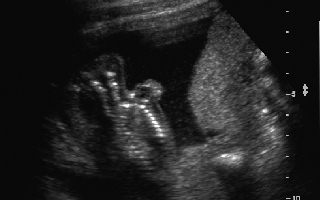

Anencephalic Fetus Case # 14496 Fetus presented without MSAFP levels G1 P0 AB0. Images demonstrate lack of a cranial vault. Fetus was aborted.